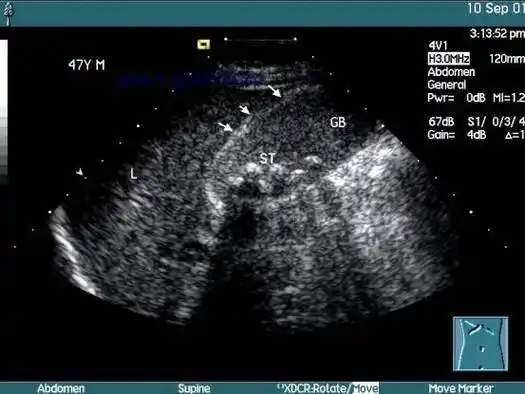

2022年2月14日,他再次返院复查,b超检查显示"保胆术后9年余,胆囊内

经典图片:蜂巢样胆囊_症状